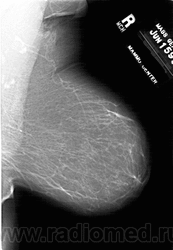

Со старением железистая ткань постепенно исчезает: прозрачность жировой ткани становится преобладающей с несколькими каркасами, связанными с опорными волокнистыми структурами.

Жирная (не плотная) грудь

Умеренно плотная грудь

Плотная грудь

Маммограммы представляют собой изображения структур, проецируемых на плоскость: плотная грудная маммограмма, следовательно, состоит из многих других структур, которые необходимо проанализировать, чем более жирная, пустая грудь. По этой причине диагностировать рак молочной железы труднее для моложе, чем для пожилых женщин.

Нажмите на миниатюрные картинки, чтобы получить увеличенный размер.